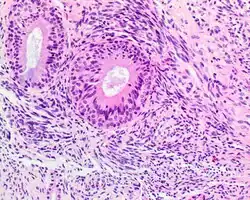

| A high-power view of a hematoxylin- and eosin-stained slide showing respiratory epithelial inclusions within a spindled cell neoplasm showing characteristics of a biphenotypic sinonasal sarcoma | |

- Infiltrative, highly cellular spindled cell neoplasm is poorly circumscribed and unencapsulated. Bone destruction or invasion is common. The cells show medium to long fascicles (nerve fibers), with a herringbone pattern. The cells are remarkably uniform with elongated nuclei. Delicate strands of intercellular collagen without ropy or dense deposition are seen. A very characteristic concurrent surface-type respiratory epithelial proliferation is found from the surface or in small cystic spaces around the cancer cells, often forming glands. The background may have a rich vascularity and usually has a small number of scattered lymphocytes. Extra growths or mitoses are rare, while necrosis, ulceration, and hemorrhage are usually absent.